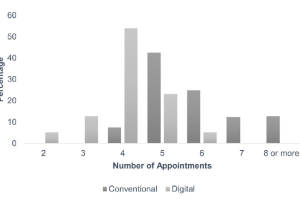

CLINICAL PERFORMANCE OF CAD-CAM-FABRICATED COMPLETE DENTURES: A CROSS-SECTIONAL STUDY

Paola C. Saponaro, DDS, MS,a Burak Yilmaz, DDS, PhD,b Reza H. Heshmati, DDS, MPH, MS,c and Edwin A. McGlumphy, DDS, MSd. Purpose. The purpose of this retrospective study was to evaluate clinician experience with digital CD fabrication attempted in a 2-visit protocol. The actual number of appointments required for insertion and the number of postinsertion adjustment visits, and whether the incidence of treatment complications was related to operator experience were recorded and evaluated.

COMPARISON OF TREATMENT OUTCOMES IN DIGITAL AND CONVENTIONAL COMPLETE REMOVABLE DENTAL PROSTHESIS FAVRICATIONS IN A PREDOCTORAL SETTING

Mathew T. Kattadiyil, BDS, MDS, MS,a Rami Jekki, DDS,b Charles J. Goodacre, DDS, MSD,c and Nadim Z. Baba, DMD, MSDd. Purpose. This prospective clinical study was conducted to compare clinical treatment outcomes, patient satisfaction, and dental student preferences for digitally and conventionally processed CRDP in a predoctoral setting.